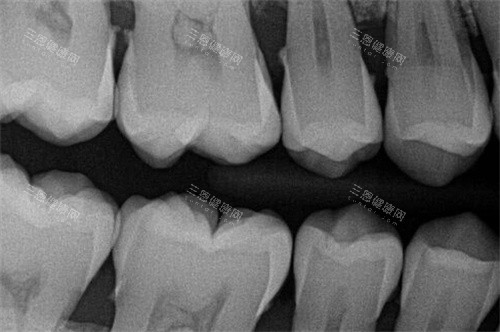

小牙片